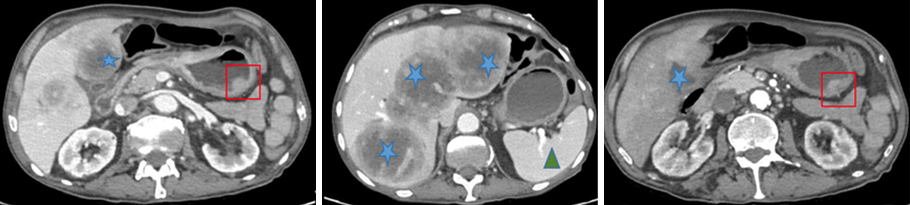

Figure 4 (Élisabeth Capelle, La Revue du Praticien)

Dans le carré rouge : masse gastrique suspecte.

Étoiles bleues : métastases hépatiques.

Triangle vert : rate d’aspect normal.